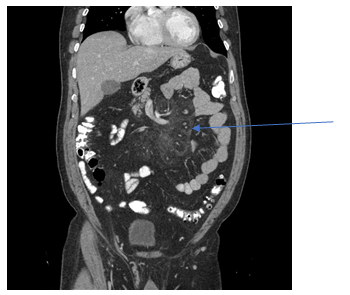

A 58-year-old white male with a past medical history of coronary artery disease, gastroesophageal reflux disease, hyperlipidemia and partially incarcerated umbilical hernia was referred to the surgeon by his primary care physician due to chronic right lower quadrant abdominal pain associated with one episode of non-bloody vomiting. He denied change in bowel habits, weight loss or blood in stools. On physical examination the only positive finding was that the abdomen was soft with mild tenderness in the right low quadrant and no peritoneal signs. Complete Blood Count (CBC), Basic Metabolic Panel (BMP) and Liver Function Tests (LFT) were essentially within normal limits. The total cholesterol was 316mg/dl, high density lipid was 38mg/dl and triglycerides level were 203mg/dl. Lactic acid, Erythrocyte Sedimentation Rate (ESR) and C-Reactive Protein (CRP) were also normal. CT abdomen/pelvis with contrast revealed increased mesenteric attenuation with induration and associated lymphadenopathy within the inferior midline abdomen (Figure 1). Lymph nodes demonstrated a halo of spared fat (Figure 2) consistent with sclerosing mesenteritis. The patient subsequently underwent elective laparoscopic epigastric and umbilical herniorrhaphy with mesh. The surgical specimen pathology consisted of adipose tissue. The histologic finding was mesothelial lined fibrous tissue showing chronic inflammation. It negative for malignancy including lymphoma. Upper Gastrointestinal Endoscopy (EGD) was performed and was negative for malignancy and Helicobacter Pylori. Patient was discharged from the hospital without any complications with pain medications. On subsequent follow up, the patient continued to complain of chronic mild right lower abdominal pain that was controlled with non-steroidal anti-inflammatory drugs . Repeat CT abdomen/pelvis one year later showed stable appearance of inflamed fat at the root of mesentery with numerous small lymph nodes (Figure 3).

Figure 1 Mesenteric attenuation with induration and associated lymphadenopathy within the inferior midline abdomen.